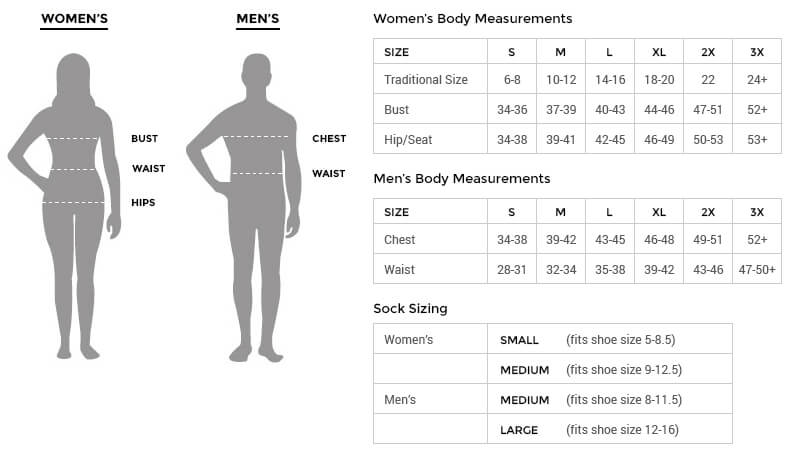

Images

| IHC analysis of ki67 (GB111141). Sample: Mouse placenta (Paraffin), 4% PFA (G1101) 12-24h. Antigen retrieval: Citrate buffer (pH 6.0) (G1201), pressure cooker 2min. Blocking buffer: 3% BSA in PBS (GC305010), RT, 30min. Primary antibody: 1: 1000, 4°C overnight. Secondary antibody: HRP Goat Anti-Rabbit lgG (GB23303), 1: 200 RT 1h. |